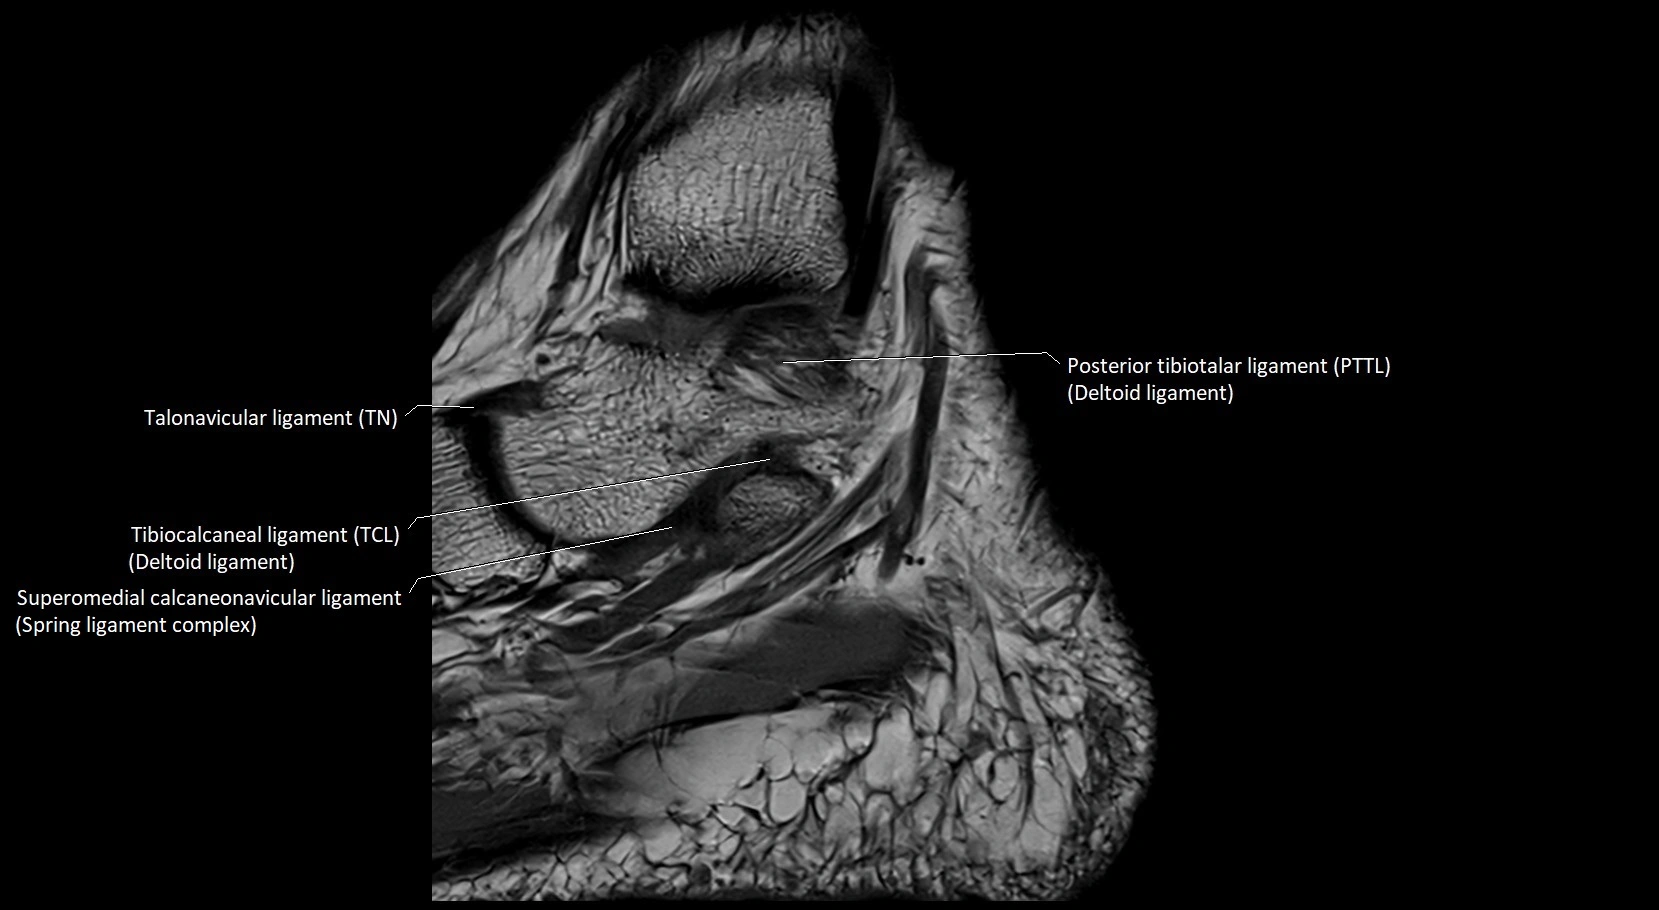

MRI image

image